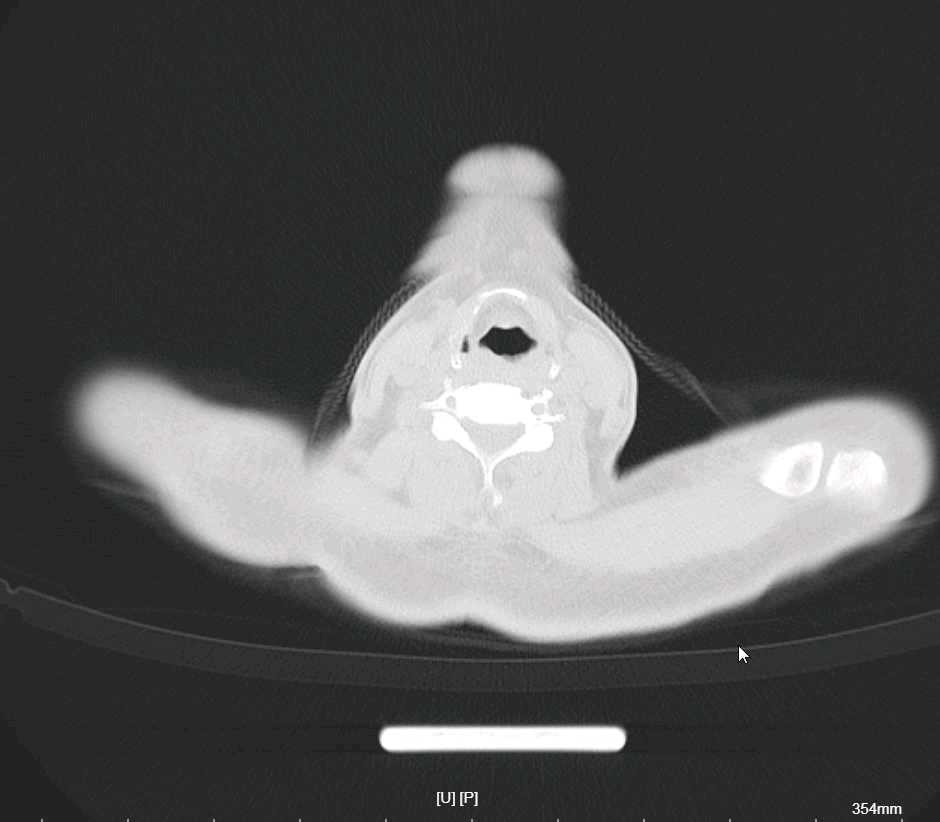

李梦杰huxi 达人已点赞患者性别:男性。

患者年龄:68岁。

主诉:反复畏寒,发热伴咳嗽4天

简要病史:有脑梗死病史半年余,现遗留左侧肢体无力,有高血压病史

辅助检查:

现患者就是一直发烧,最好体温38.2,血常规,超敏c,降钙素,心肌酶都正常